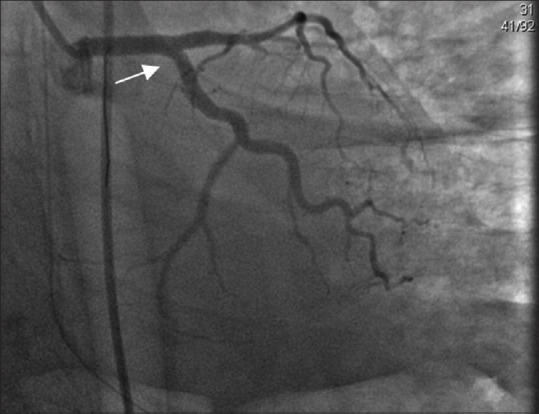

Spontaneous coronary artery dissection is becoming an important cause of acute coronary syndrome, particularly among young women. Its association with female gender, pregnancy, and postpartum period and emotional stress differentiate it from atherosclerotic heart disease. In recent years, there has been more awareness and improved diagnostic and management capabilities, which in turn has increased the diagnostic yield, although knowledge gaps remain. In the present case, a 36-year-old female, who was at 1-month postpartum period, presented with ventricular fibrillation and cardiac arrest. The clinical course was associated with pulmonary hemorrhage. The patient had no current atherosclerotic risk factors, only a family history of sudden cardiac arrest in her mother and sister. She underwent a coronary angiogram, which revealed spontaneous coronary artery dissection (SCAD) in both the left anterior descending and left circumflex artery. Percutaneous coronary intervention was performed but the clinical course was associated with pulmonary hemorrhage. Bronchopulmonary lavage was performed as a diagnostic and therapeutic intervention, and she was discharged in good health. SCAD is an important differential diagnosis in young females presenting with acute coronary syndrome or cardiac arrest. Early recognition and diagnosis are important to decrease the high mortality rate of this disease.